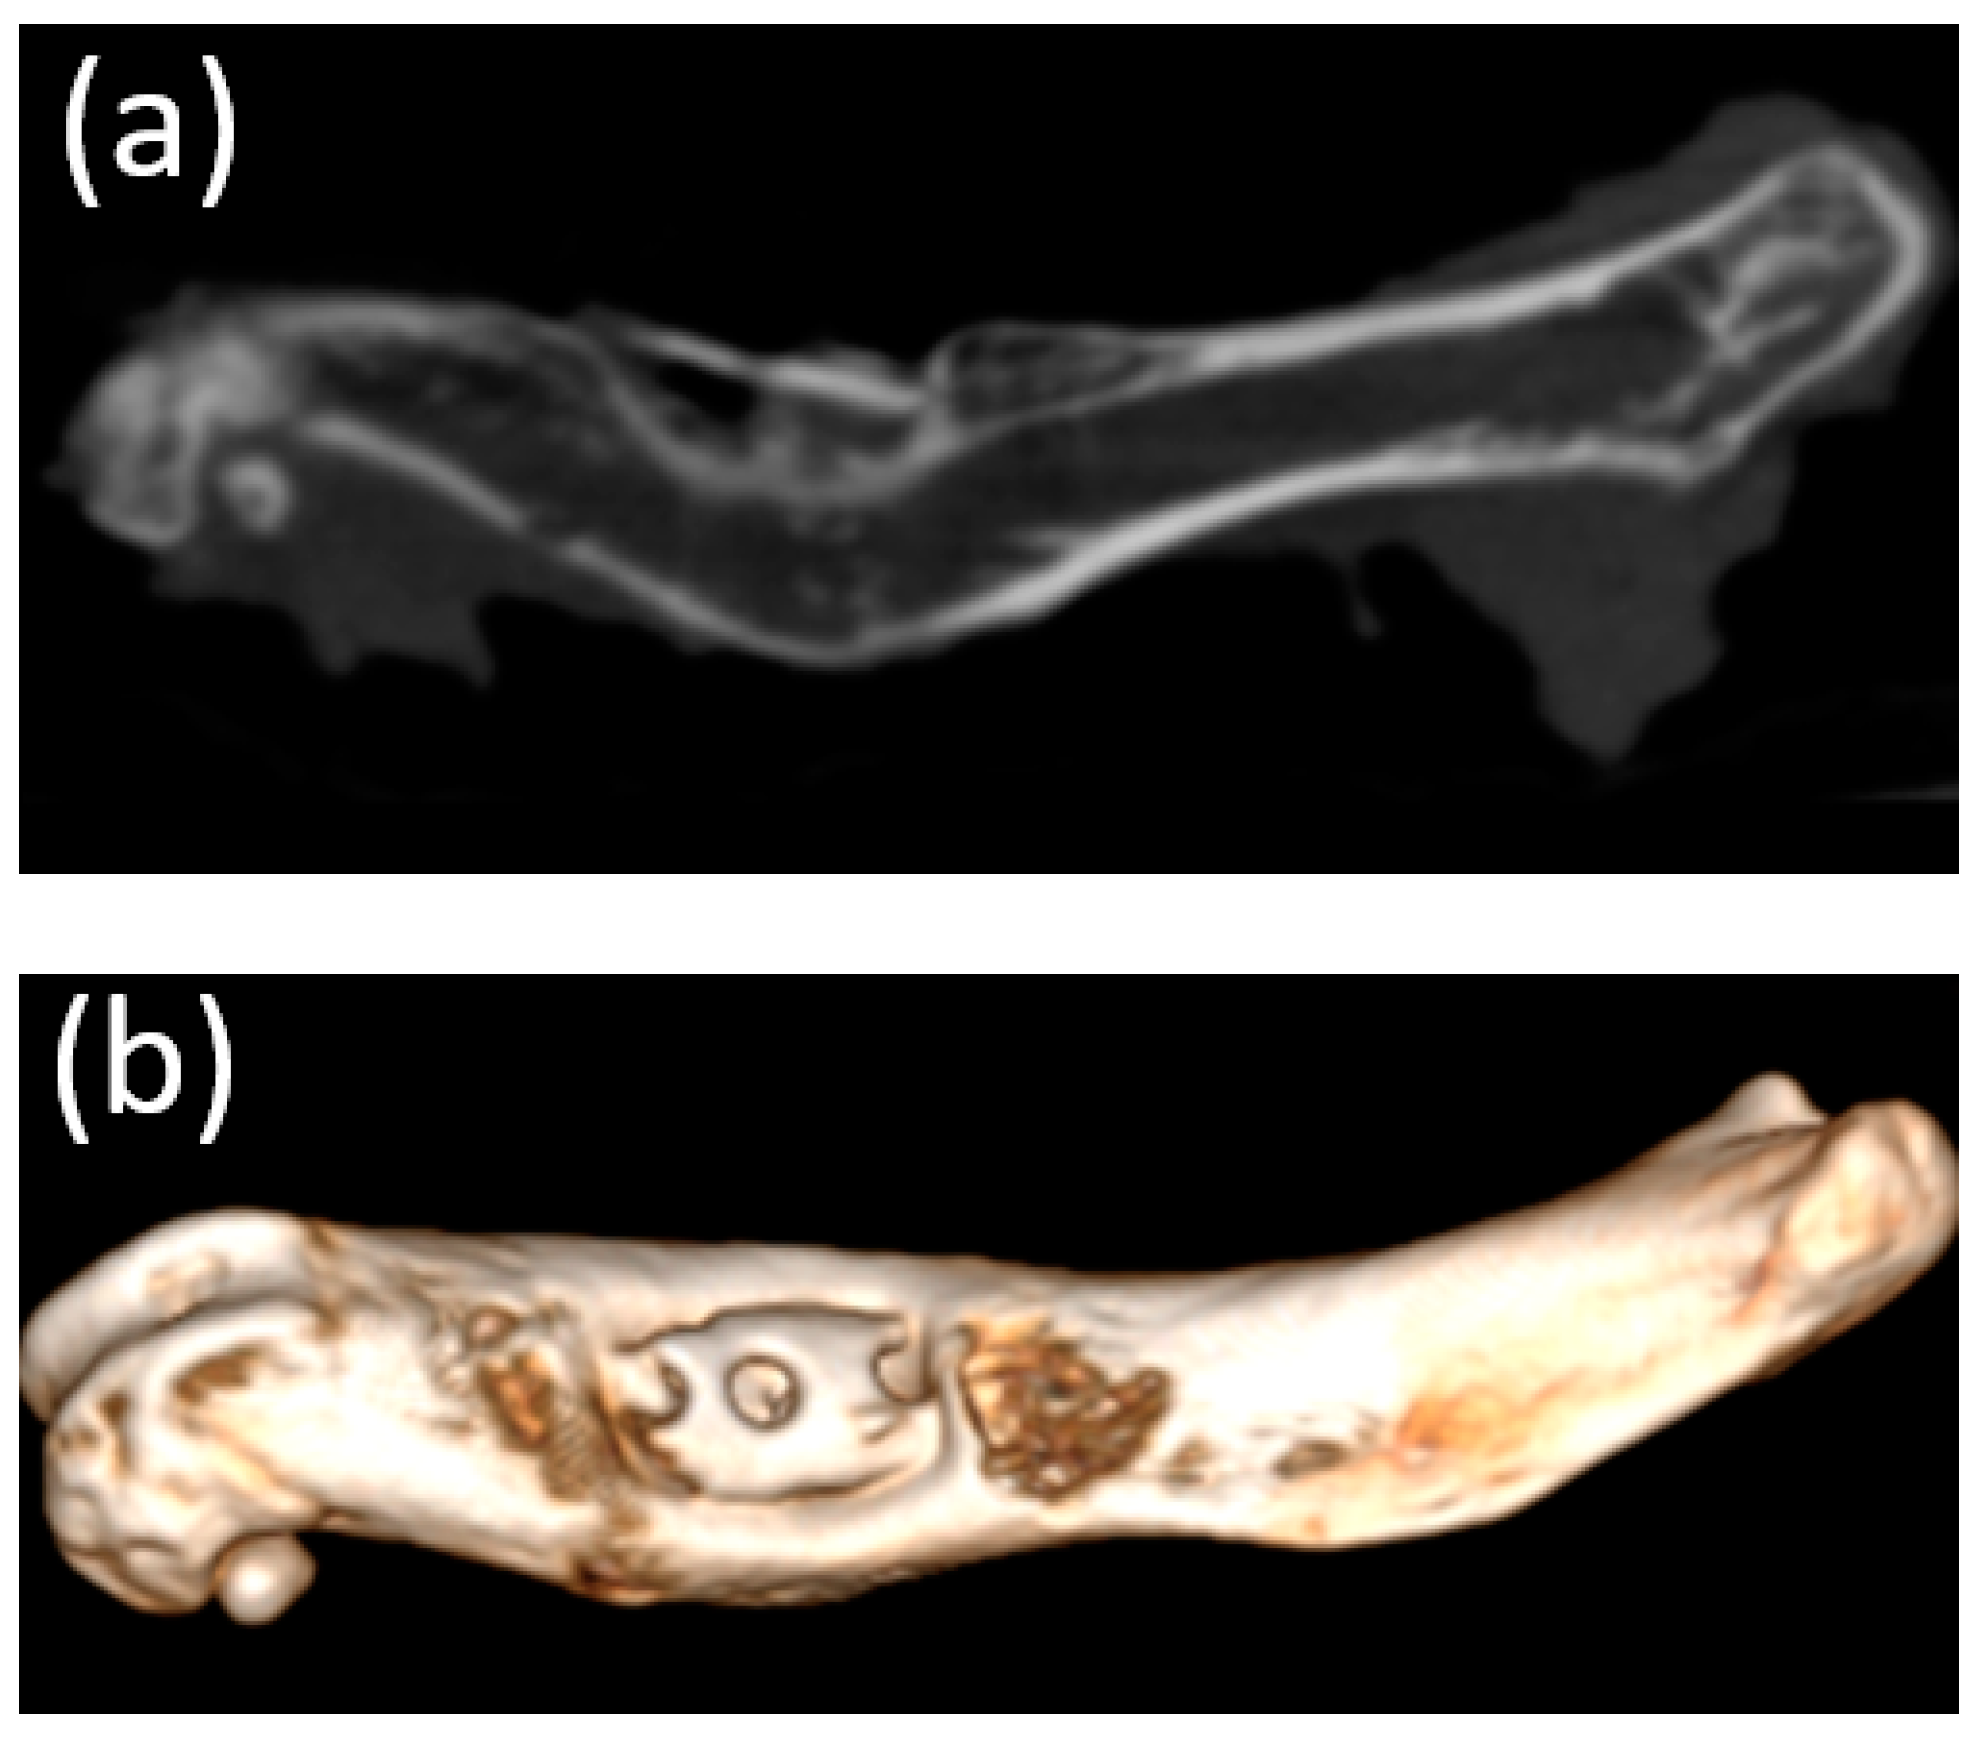

3.4. Cone Beam Computed Tomography

3.5. Micro-CT